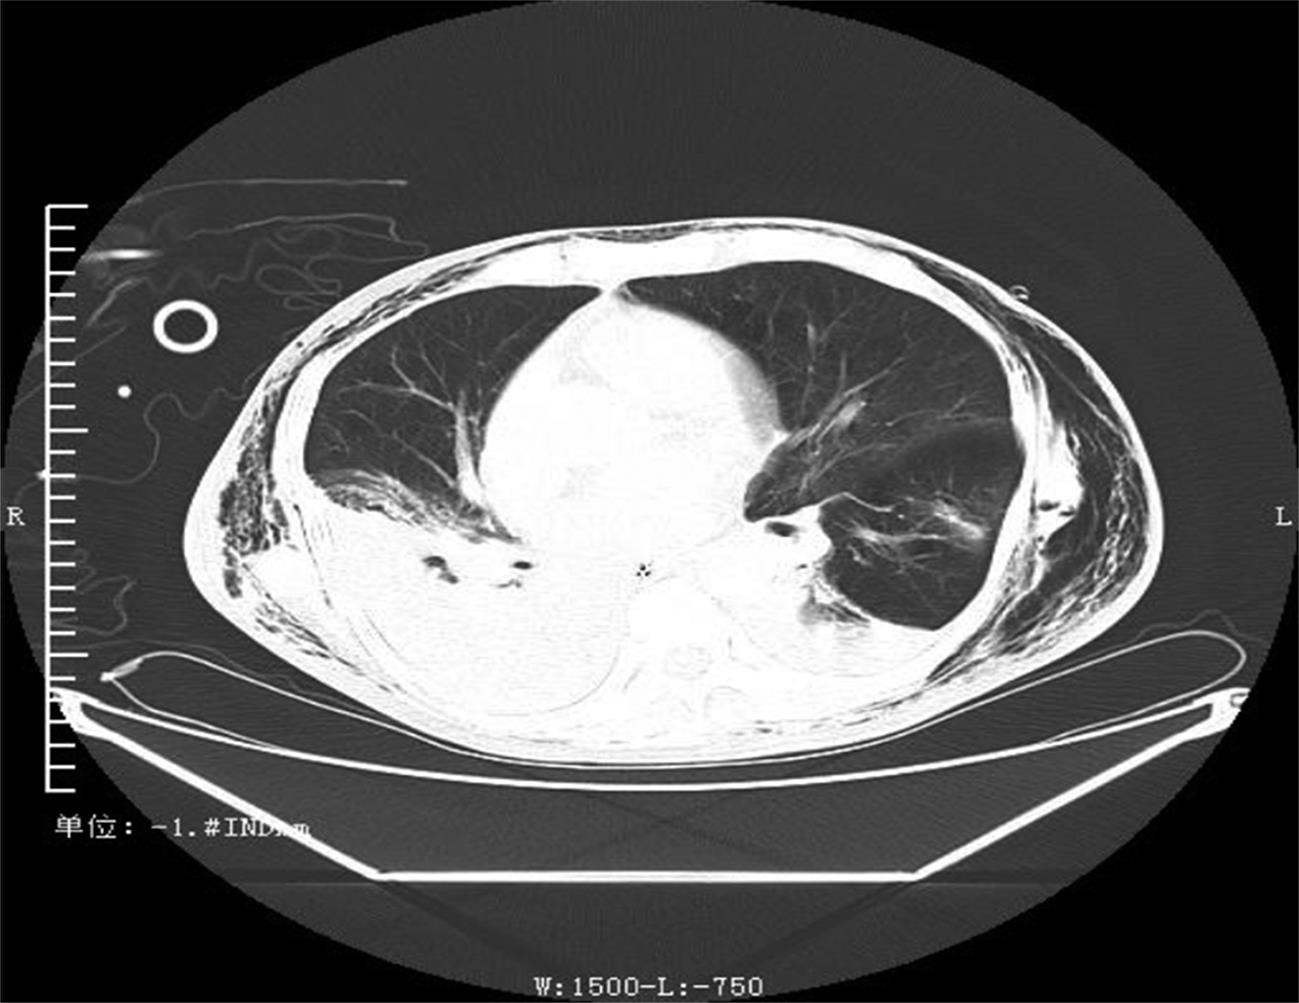

• 基于宏基因组二代测序诊断15例鹦鹉热衣原体肺炎临床特征与诊治分析

2023, 48(6):715-720. DOI: 10.13406/j.cnki.cyxb.003248

摘要 (49) HTML (29) PDF 858.28 K (202) 评论 (0) 收藏

摘要:目的 探讨和分析少见鹦鹉热衣原体肺炎的临床特征、诊治及预后,以期提升临床相关学科领域对该病的认识。方法 回顾性研究赣南医学院第一附属医院2017年1月至2022年12月确诊的15例鹦鹉热衣原体肺炎患者的临床资料,总结并分析该病的临床特征、诊断与鉴别要点,同时检索国内外文献资料对鹦鹉热衣原体肺炎的最新诊疗进展予以系统性讨论。结果 纳入本研究的15例鹦鹉热衣原体肺炎患者中,男性10例(66.67%),女性5例(33.33%),年龄62(32~79)岁,禽类接触史14例(93.33%),基础疾病史8例(53.3%),转化为重症肺炎5例(33.33%)。15例患者中,白细胞计数(white blood cell count,WBC)正常8例(53.3%),WBC升高5例(33.3%),WBC减低2例(13.3%);血红蛋白(hemoglobin,HGB)正常9例(60.0%),减低6例(40.0%);中性粒细胞百分比(neutrophils,NE)升高13例(86.7%);所有患者(100.0%)C反应蛋白(C-reactive protein,CRP)均显著升高;13例(86.67%)患者降钙素原(procalcitonin,PCT)升高;12例(80.0%)患者乳酸脱氢酶(lactate dehydrogenase,LDH)升高;11例(73.33%)肝功能异常;8例(53.33%)肾功能异常;6例(40.0%)凝血功能异常;13例(86.7%)电解质紊乱。此外,11例(73.33%)患者动脉血气分析显示不同程度血氧分压降低,8例(53.33%)氧合指数(oxygenation index,OI)低于300 mmHg,4例(26.67%)患者无明显呼吸困难,未进行动脉血气分析检查。本研究所有患者均已完善经支气管镜检查,并获取支气管肺泡灌洗液(bronchoalverolar lavage fluid,BALF)行宏基因组二代测序(metagenomic next-generation sequencing,mNGS)检测,检出的病原体除鹦鹉热衣原体外,所有患者均合并多种病原体感染。15例患者均已完善肺部电子计算机断层扫描(computed tomography,CT)等影像学检查,单侧肺部实变7例(46.67%),双侧实变8例(53.33%);9例(60.0%)患者伴有胸腔积液,部分患者可以表现出多种影像学表现,包括实变影、磨玻璃影、团块样实变影、反晕征、纵隔和肺门淋巴结肿大等。15例鹦鹉热衣原体肺炎患者在确诊后均予规范抗感染治疗,其中5例重症肺炎患者中2例患者予体外膜肺氧合(extracorporeal membrane oxygenation,ECMO)辅助治疗,所有患者均未见治疗相关不良反应或不良事件,平均住院日为13.9 d。本研究所有患者未见死亡,均好转出院。结论 鹦鹉热衣原体肺炎临床特征及表现缺乏特异性,易出现重症化,经支气管肺泡灌洗液予mNGS检测可精准确诊,早期予四环素类及喹诺酮类抗生素可最大程度改善患者预后。